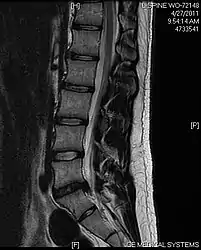

- Magnetic resonance imaging is the gold standard study for confirming a suspected LDH. With a diagnostic accuracy of 97%, it is the most sensitive study to visualize a herniated disc due to its significant ability in soft tissue visualization. MRI also has higher inter-observer reliability than other imaging modalities. It suggests disc herniation when it shows an increased T2-weighted signal at the posterior 10% of the disc. Degenerative disc diseases have shown a correlation with Modic type 1 changes. When evaluating for postoperative lumbar radiculopathies, the recommendation is that the MRI is performed with contrast unless otherwise contraindicated. MRI is more effective than CT in distinguishing inflammatory, malignant, or inflammatory etiologies of LDH. It is indicated relatively early in the course of evaluation (<8 weeks) when the patient presents with relative indications like significant pain, neurological motor deficits, and cauda equina syndrome. Diffusion tensor imaging is a type of MRI sequence used for detecting microstructural changes in the nerve root. It may be beneficial in understanding the changes that occur after herniated lumbar disc compresses a nerve root, and might help in differentiating the patients that need surgical intervention. In patients with a high suspicion of radiculopathy due to lumbar disc herniation, yet the MRI is equivocal or negative, nerve conduction studies are indicated.[43] T2-weighted images allow for clear visualization of protruded disc material in the spinal canal.

MRI scan of cervical disc herniation between C5 and C6 vertebrae.

MRI scan of large herniation (on the right) of the disc between L4 and L5 vertebrae

A rather severe herniation of the L4–L5 disc